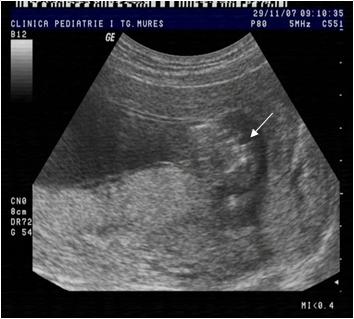

Fig. nr.130 Os nazal evident la o sarcina de 12 saptamani ( sageata)